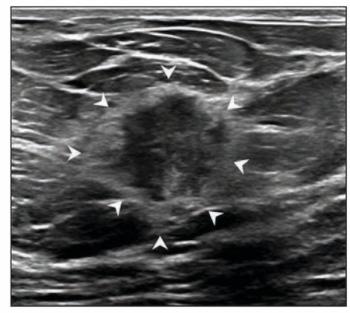

For masses interpreted as BI-RADS category 4 and 5 presentations on breast ultrasound, the authors of a new study found that the presence of echogenic rind had an 81 to 85 percent specificity for malignancy.